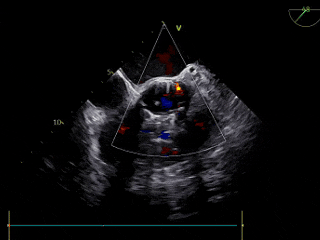

TEE

左室短轴切面见二叶瓣畸形、长轴切面见重度反流。

术后TEE评估

TEE超声评估微量瓣周漏,测压差7mmHg,反流改善明显。